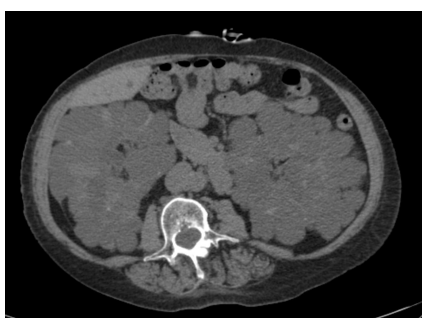

This is the case ofa 63 y/o female patient, with a past medical his. tory of adult polycystic kidney disease (ADPKD), hypertension, hypothyroidism, and hypercholesterolemia that was started on peritoneal dialysis one month ago. Patient presented to emer. gency department with shortness of breath and fatigue for the past 3 weeks that was getting worse, causing fatigue and ortho- pnea. Physical examination was remarkable for decreased breath sounds on the right side, no jugular venous distention, no pe- ripheral edema, and patent peritoneal dialysis tunneled catheter in the abdomen, Portable chest X-ray reported diffuse right White lung with mass-effect towards the left. The Chest CT scan with- out IV contrast reported large right-sided pleural fluid collection with near total collapse of the lung and polycystic kidney disease. Due to large amount pleural fluid, surgery services were consult- ed for chest tube placement, The analysis result of the pleural flu• id was consistent with transudate fluid and elevated glucose level (69 mg/dl), She had relief after chest tube drainage and no recur- rence of pleural effusion occurred after patient was switched to Findings suggest a pleuroperitoneal leak, due to given history of ADPKD with pleural effusion that occurs early after peritoneal dialysis initiation, and no other clinical findings of fluid overload